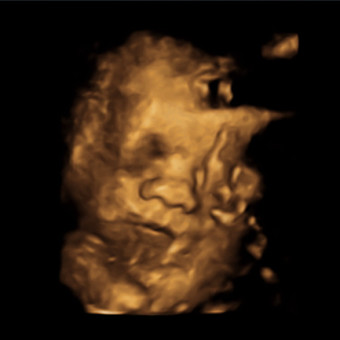

Kara & Blaine Melton

We cannot wait for our baby boy, Ridge, to arrive! Thank you for helping us celebrate our blessing.